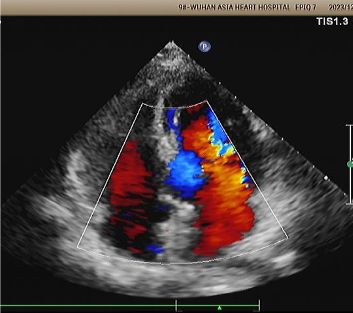

1-Year Echo:

No visible disc structures – replaced by 8mm tissue thickening at the septal implant site.

Zero residual shunt (rest or post-Valsalva).

Complete device absorption confirmed.